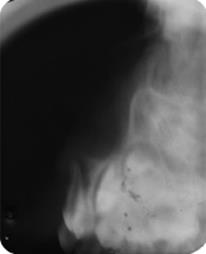

Radiograficamente, (radiografia periapical anterior modificada e radiografia lateral de Fazzi), os dentes #61 e #62 apresentavam- se sem fratura da tábua óssea e lesão dos germes dos dentes permanentes (Figuras 1B e 2). Sendo assim, o tratamento de escolha foi aguardar e acompanhar a reerupção espontânea dos dentes afetados.

O exame radiográfico também é essencial em casos de traumatismos dentários envolvendo os tecidos de suporte, a fim de avaliar a condição radicular, a relação com estruturas adjacentes e a existência de lesões periapicais, fragmentos ósseos e corpos estranhos. As técnicas radiográficas mais utilizadas nas luxações intrusivas são periapical anterior modificada e lateral de Fazzi, que permitem avaliar a direção do deslocamento do dente envolvido para palatina ou vestibular.24